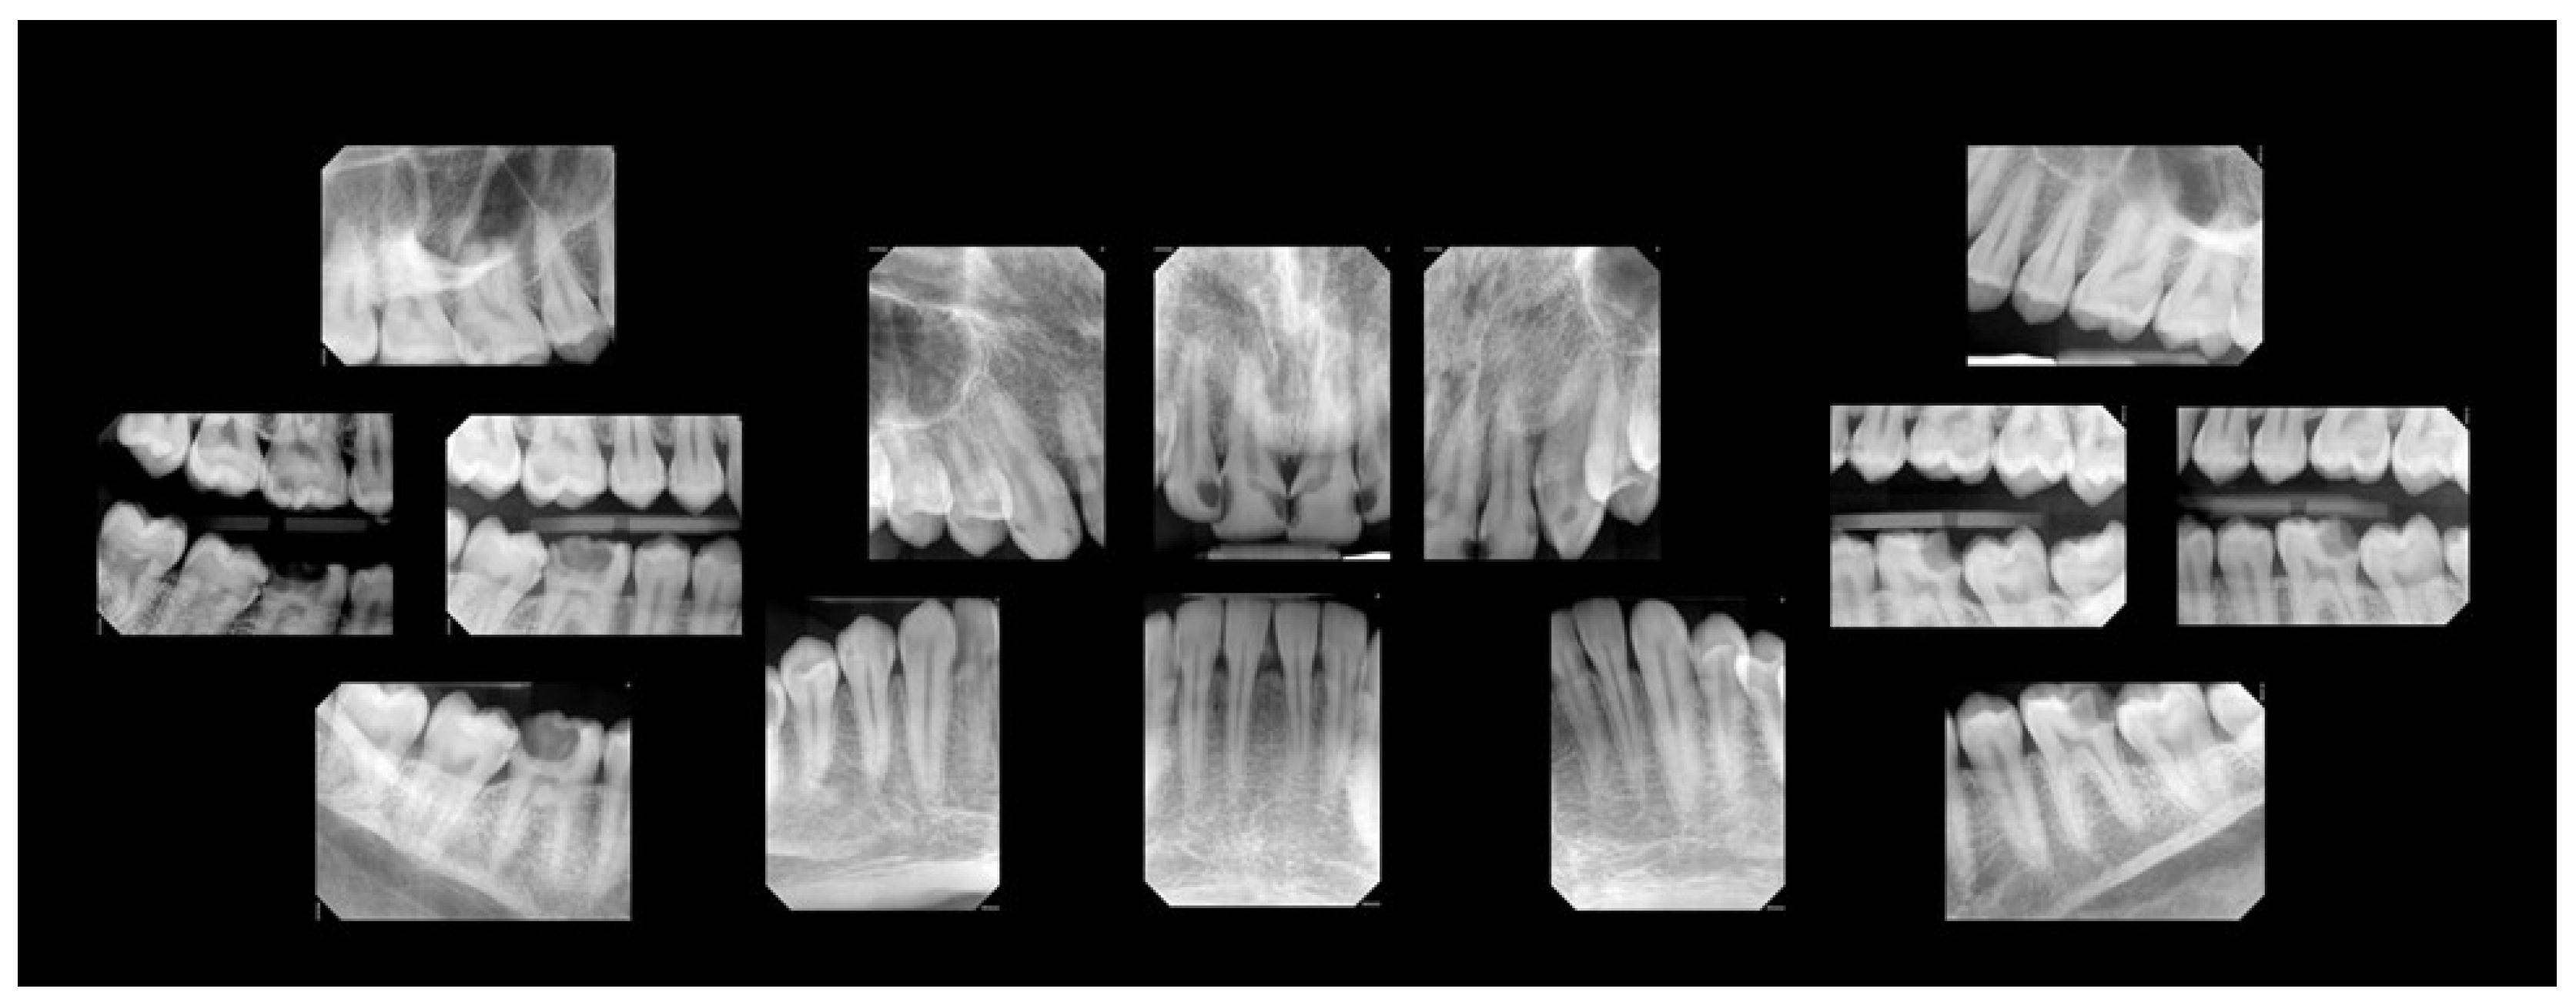

A comprehensive oral examination, including intraoral photographs and full-mouth radiographs (Figure 1 and Figure 2), was conducted. The examination revealed that the patient had a full set of 32 teeth. Among these, 25 teeth exhibited active decay affecting single and/or multiple surfaces, six had incipient carious lesions, and one tooth was sound. Fractures were identified on the incisal surfaces of teeth numbered 41, 31, and 32. Furthermore, the distal-occlusal lingual wall of tooth 46 was found to be fractured, and tooth 28 exhibited extrusion.

Figure 1. Pre-treatment intraoral photographs.